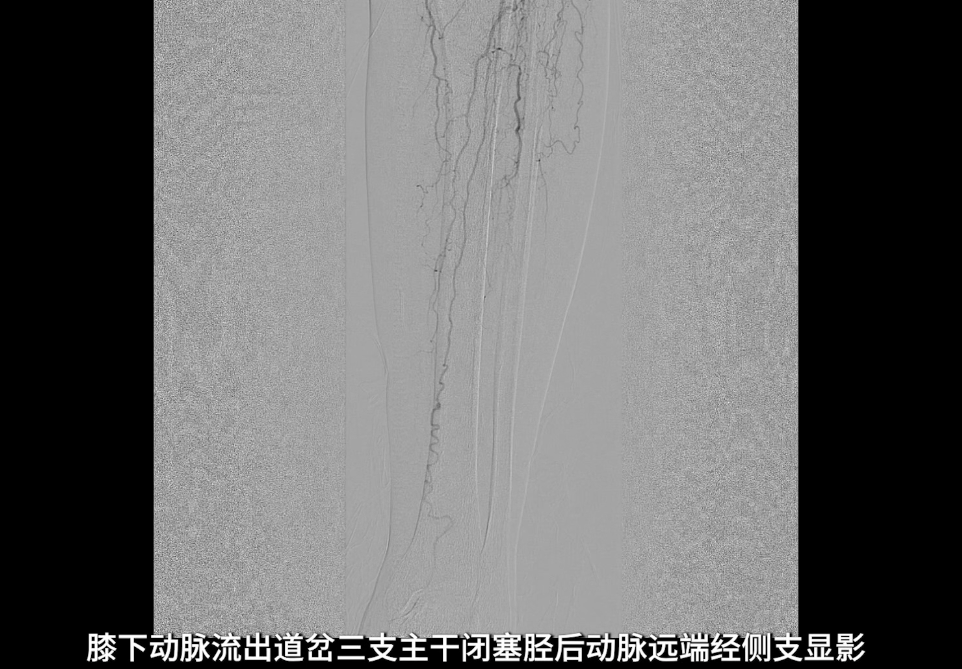

膝下动脉三支主干均闭塞,胫后动脉远端经侧支循环显影;腓动脉远端为“休眠血管”,通过与胫后动脉的交通支实现逆向显影。

术后造影验证:股浅动脉管腔恢复通畅,无明显残余狭窄,局限夹层未对血流造成影响,无需植入补救性支架;膝下腓动脉流出道通畅,胫后动脉至足底动脉血流连续,足部血流灌注显著改善。